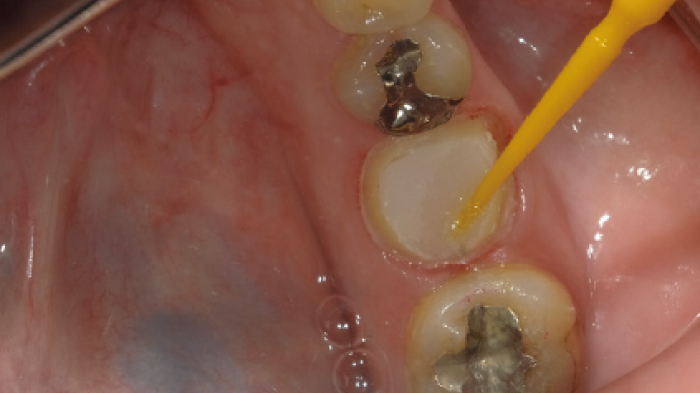

Une vue après le retrait de la restauration provisoire et du ciment temporaire. On peut observer qu'une partie du ciment temporaire reste encore sur la surface proximale distale.

Traitement de sablage sur l'ancrage. La surface de l'ancrage peut être agrandie ; le ciment temporaire peut être complètement éliminé. Il est difficile de nettoyer l'ancrage uniquement avec des outils manuels.

Application du Primer après le sablage de la zone d'ancrage.